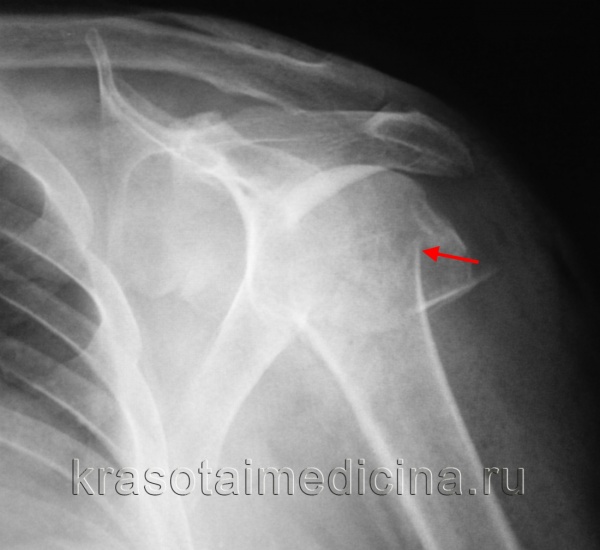

КТ плечевого сустава. Оскольчатый перелом хирургической шейки плечевой кости со смещением отломков. Дистальный отломок (красная стрелка) вколочен в проксимальный отломок (синяя стрелка).

Возможен перелом головки, отрыв малого или большого бугра, перелом анатомической и хирургической шейки плеча. Наиболее распространены переломы хирургической шейки, причем подавляющую часть пострадавших составляют люди пожилого возраста. Причиной перелома обычно становится падение на локоть, плечо или отведенную руку.

Пациент предъявляет жалобы на боли в области плечевого сустава. Вколоченные переломы сопровождаются нерезким отеком, болезненностью при попытке активных движений. Пассивные движения ограничены незначительно. При переломе со смещением клиническая картина более яркая. Пострадавшего беспокоят выраженные боли. Выявляется умеренный отек, деформация области сустава и укорочение конечности. Определяется крепитация (хруст костных фрагментов). Диагноз уточняют по результатам рентгенографии. При внутрисуставном переломе может быть проведено УЗИ плечевого сустава.